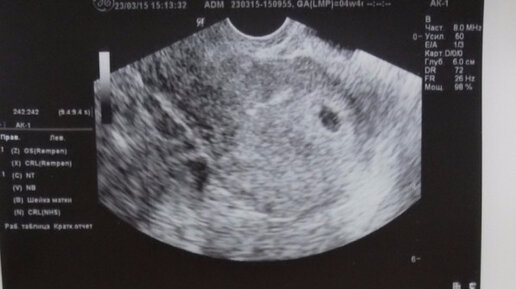

Что значат показатели УЗИ при беременности на разных сроках

Каждая будущая мама желает как можно быстрее познакомиться со своим малышом, увидеть, какой он, и запечатлеть в памяти этот неповторимый момент. Однако сделать это можно только после 9 месяцев вынашивания, а ведь как не хочется ждать столь длительный срок! Благодаря УЗИ при беременности вы можете увидеть кроху и узнать, как хорошо ему живется в животике. УЗИ при беременности: цель обследования Исследование ультразвуком позволит вам: Зачастую специалисты в этом вопросе немногословны, и у женщины остается масса вопросов о проведенном УЗИ...